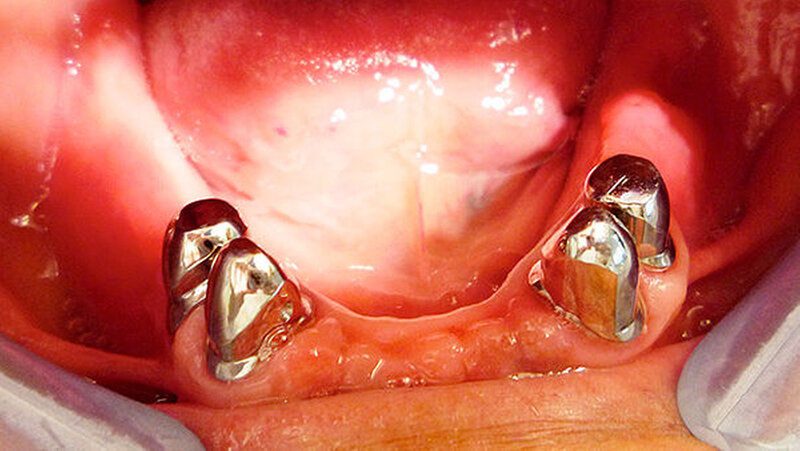

Die Abbildungen 4 bis 8 zeigen die Situation nach vier monatiger ZE-Tragezeit. Nach ausgiebiger Extraktionstherapie und parodontaler Behandlung der Restzähne wurde im Oberkiefer eine Cover-Denture-Totalprothese inseriert und im Unterkiefer eine parodontal abgestützte Teleskopprothese mit verblendeten Teleskopen 34,35,44,45.

Es sei dazu folgendes anzumerken, schreiben die Behandler: D"ie Einstellung des Patienten zu seiner Mundhygiene hat sich plötzlich grundlegend geändert. Die Prothese zeigt nach vier Monaten einen ausgezeichneten Pflegezustand, obwohl der Patient starker Raucher ist und vorher ja die bekannten parodontalen Probleme hatte. Alle Pfeilerzähne sind absolut fest und ohne Lockerung, obwohl sie vorher noch Lockerungsgrad I zeigten. Auch die Pfeilerteleskope sind sehr gut gepflegt. Der Patient hat seine Recalltermine nun zuverlässig wahrgenommen."